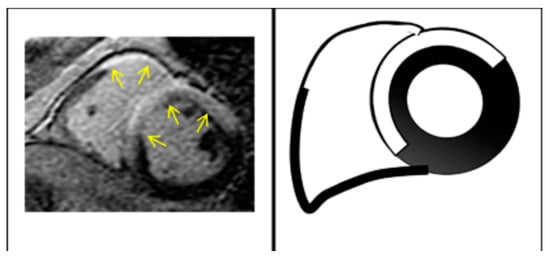

2.2. Cardiac Magnetic Resonance